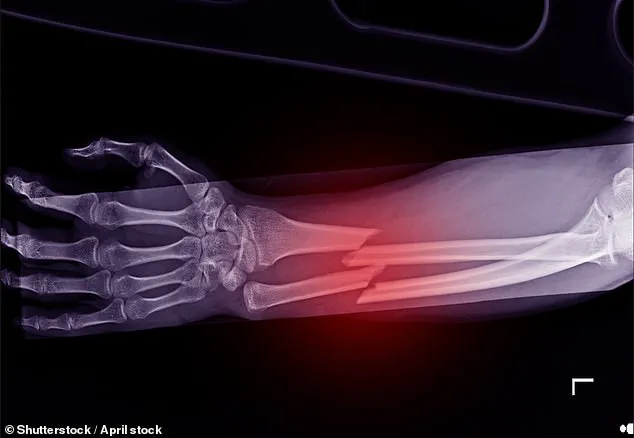

Urgent Call to Expand Fracture Services as Campaigners Warn of Rising Osteoporosis-Related Deaths

Delays in the rollout of screening clinics for a bone-thinning disease are putting women’s lives at risk, say campaigners.

The disease affects 3.5 million people in the UK, and one in two women over 50 will break a bone because of osteoporosis.